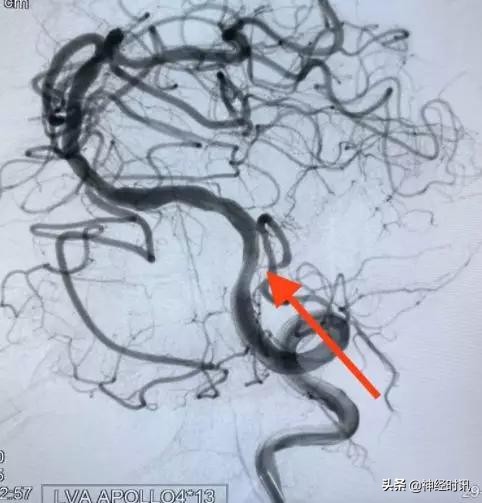

在与家属充分沟通后还是决定治疗。我们进一步精细化了手术方案,决定术中保护小脑后下动脉。我们先放置一条柔软的微导管在小脑后下动脉(绿箭),然后再对狭窄实施扩张(蓝箭)。这样就极大地提高了保护分支的概率。

扩张完后再置入支架。经过这样的技术细化,我们可以看到在狭窄被治疗的同时,很好地保护了分支(红箭)。